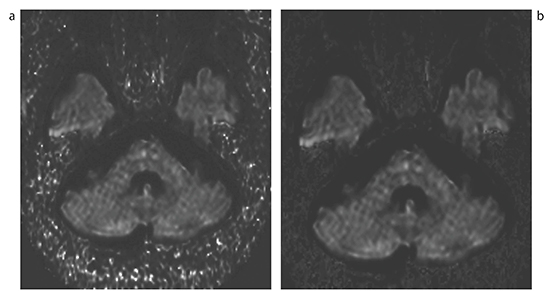

cDWIは,2つ以上のb値を用いて仮想のb値の画像を作成する手法である。当院ではルーチン検査で撮像するDWI b=1000s/mm2を用い,b=0,1000s/mm2の2つから作成している。作成は特殊な撮像をする必要もなく,簡便な後処理を行うことでいつでも可能である。注意点として,擬似的にb値を大きくするにつれて高輝度ノイズと呼ばれるcDWI特有の現象が発生する。しかし,作成時にb値をスライダーバーで変化させる際,リアルタイムで観察できるため,所見と高輝度ノイズを見分けることは可能だと考える(図1)。また,高輝度ノイズはフィルタで閾値を設定し,除去することができる(図2)。

図2 フィルタによる高輝度ノイズの除去

a:cDWI=3000s/mm2フィルタなし

b:cDWI=3000s/mm2フィルタあり